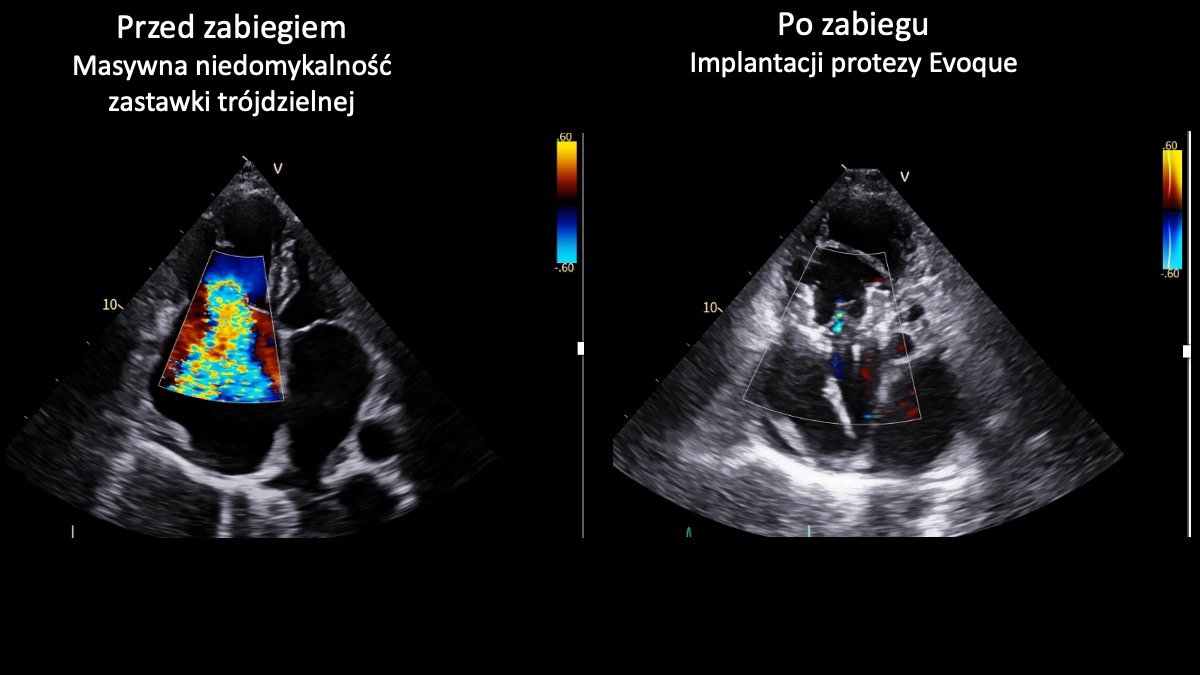

Zastawka trójdzielna znajduje się w prawej części serca i działa jak „zawór”, który zapewnia prawidłowy przepływ krwi w jednym kierunku. W przypadku niedomykalności nie zamyka się szczelnie, przez co część krwi cofa się, zamiast płynąć dalej. Masywna niedomykalność oznacza bardzo zaawansowaną postać tej wady – cofanie krwi jest znaczne, co prowadzi do przeciążenia serca i objawów takich jak: duszność, szybkie męczenie się czy obrzęki nóg. Nieleczona może prowadzić do poważnego pogorszenia jakości życia i niewydolności serca, a w konsekwencji – do śmierci.

- Obie przeprowadzone implantacje zastawki trójdzielnej Evoque zakończyły się sukcesem. To ważny krok w rozwoju małoinwazyjnego leczenia pacjentów z zaawansowanymi wadami zastawkowymi. Dla chorych obciążonych bardzo wysokim ryzykiem operacyjnym i bez innych realnych możliwości leczenia to obecnie jedyna szansa na skuteczną terapię - podkreśla prof. Marcin Fijałkowski. – Zabiegi tego typu należą nadal do najbardziej zaawansowanych procedur w kardiologii interwencyjnej. Wykonując je w UCK, dołączyliśmy do wąskiego grona ośrodków europejskich oferujących pełne spektrum przezcewnikowego leczenia chorób strukturalnych serca, w tym wad zastawkowych – dodaje profesor.